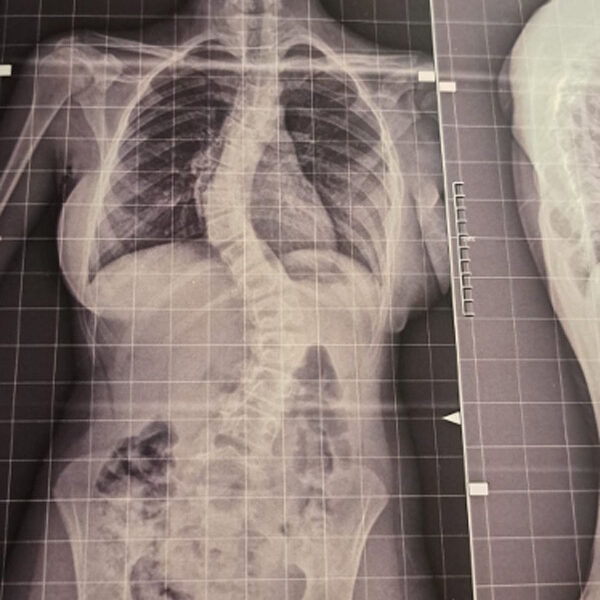

DIAGNOSI:

Scoliosi dorso lombare

Radiografia della colonna in toto pre-operatoria

Intervento chirurgico eseguito:

Artrodesi dorso lombare con osteotomie correttive

Radiografia della colonna in toto post-operatoria